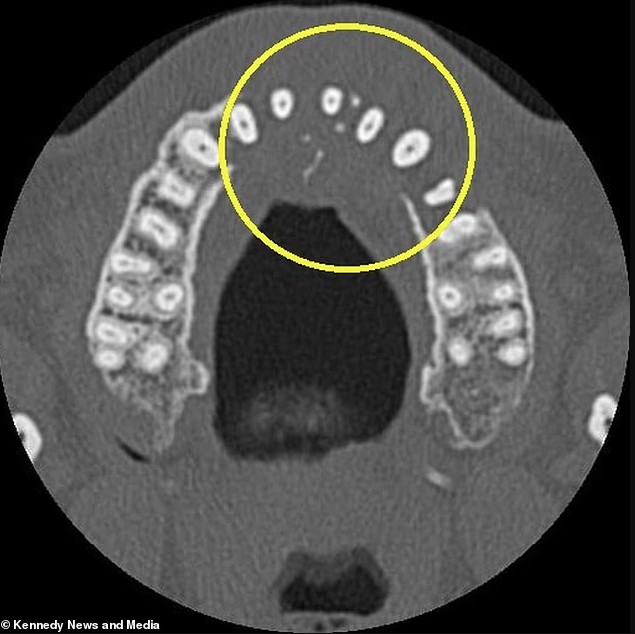

Một lần chụp CT sau đó phát hiện một khối u đang phát triển trong hốc xoang của Vieira, lan xuống phía dưới mũi.

Ảnh chụp CT cho thấy Vieira bị mất nhiều răng.

Ảnh chụp X-quang cho thấy khối u đã “ăn mòn” xuyên qua xương hàm trên của anh, và ung thư đã bắt đầu lan xuống cổ.